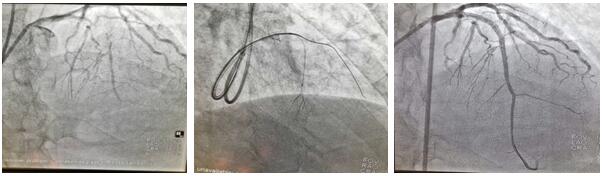

患者劉某某, 68歲男性,1月前于我院診斷:急性非ST段抬高型心肌梗死。行冠脈造影提示前降支近段100%閉塞,同側(cè)穿膈支側(cè)枝循環(huán)形成,回旋支近中段狹窄80%-90%,LAD為CTO病變,擬行完全血運(yùn)重建治療,順利于回旋支病變處植入1枚支架,術(shù)中反復(fù)嘗試各種導(dǎo)絲均未能開(kāi)通LAD血管,歷時(shí)近3小時(shí),只能放棄,擇期再處理。面對(duì)困難,面對(duì)失敗,心血管二病區(qū)左梅主任醫(yī)師團(tuán)隊(duì),反復(fù)閱片,尋找失敗原因,知難而上,勇于挑戰(zhàn),制訂新的手術(shù)策略,決定為患者第二次開(kāi)通LAD閉塞病變。在經(jīng)過(guò)充分的術(shù)前討論后于2020年7月2日第二次上臺(tái),由于患者LAD近段CTO病變,前次正向途徑介入失敗,右冠無(wú)良好側(cè)枝形成,無(wú)逆向條件,擬行乒乓技術(shù)同側(cè)微導(dǎo)管造影顯示閉塞遠(yuǎn)段,提供正向?qū)Ыz的指引,進(jìn)入遠(yuǎn)端血管真腔;若失敗,微導(dǎo)管跟進(jìn)至血管內(nèi)膜下,采用ADR(正向內(nèi)膜下重回真腔)技術(shù)完成手術(shù)。手術(shù)的重要點(diǎn)在于控制血腫的大小。術(shù)中采用同側(cè)雙指引導(dǎo)管至左冠脈開(kāi)口(乒乓技術(shù)),在一側(cè)指引導(dǎo)管送微導(dǎo)管至穿膈支中段,超選擇造影清晰顯示LAD-CTO遠(yuǎn)段,另一側(cè)指引導(dǎo)管內(nèi)反復(fù)調(diào)試FieldXT-A導(dǎo)絲順利通過(guò)閉塞病變至遠(yuǎn)段,在助手及導(dǎo)管室工作人員的全力配合下,歷時(shí)不到1小時(shí),成功完成手術(shù)。術(shù)中患者無(wú)任何不適及并發(fā)癥發(fā)生,一家人很是欣喜。